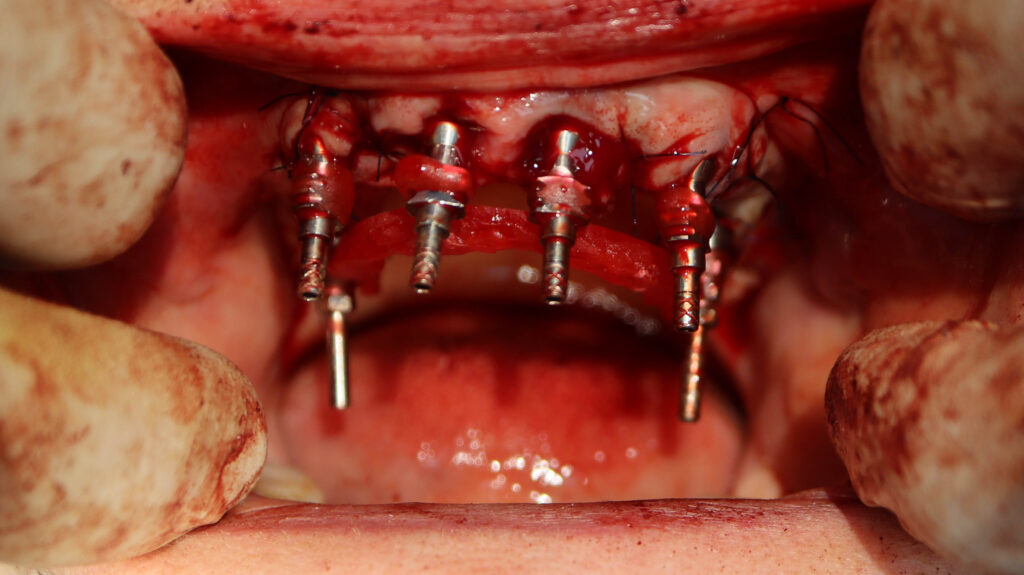

процесс работы

Что было сделано:

На верхней челюсти были удалены зубы, которые находились в неудовлетворительном состоянии, проведена комплексная имплантация по системе All-on-6, установлены 4 имплантата Megagen AnyOne и 2 скуловых имплантата NeoDent.

Фиксации имплантата внутри костной ткани (торк).

процесс имплантации